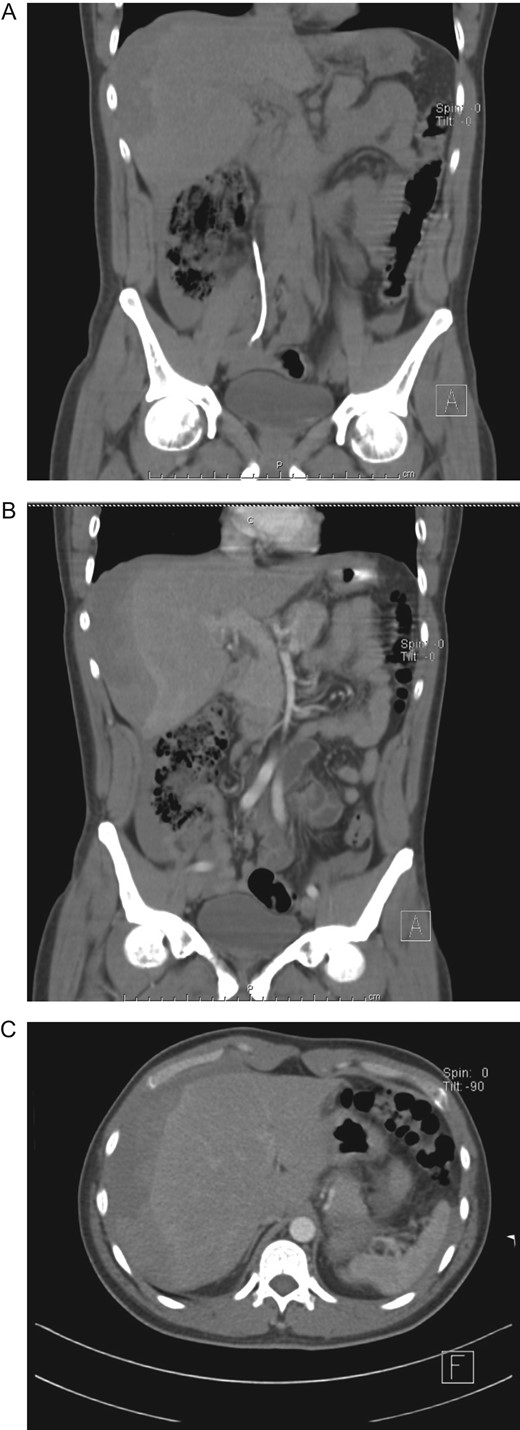

Urologist consultation was required and he underwent ureteroscopic lithotripsy without complications, the ureteral stone was removed and a right double J-stent was placed. Afterward, ESWL was decided for the right nephrolithiasis. A total of 3000 shocks were delivered at a maximum power of 15 kV and a rate of 80 shocks per minute. After the therapy was completed, the patient was discharged without any apparent complication. Nonetheless, 12 h after ESWL, severe pain appeared in his right flank, thus he presented to the emergency room. On clinical examination, a dehydrated, tachycardic and hypotensive patient was encountered. Pain was discovered on his right flank without tenderness. A contrast-enhanced abdominal CT revealed a 9 × 6 × 4 cm3 subcapsular liver hematoma, with an estimated volume of 300 ml that involved almost the entire right liver, without an active contrast material extravasation (Fig. 2A–C).

(A) CT, showing double J-stent and hepatic hematoma. (B) Contrast-enhanced CT, revealing a subcapsular liver hematoma. (C) Contrast-enhanced CT, subcapsular liver hematoma without contrast material extravasation.